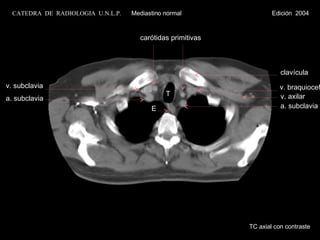

v. braquiocef. T a. subclavia v. subclavia v. axilar clavícula E a. subclavia TC axial con contraste CATEDRA  DE  RADIOLOGIA  U.N.L.P.   Mediastino normal  Edición  2004 carótidas primitivas

v. braquiocef. Ta. subclavia v. subclavia v. axilar clavícula E a. subclavia TC axial con contraste CATEDRA DE RADIOLOGIA U.N.L.P. Mediastino normal Edición 2004 carótidas primitivas